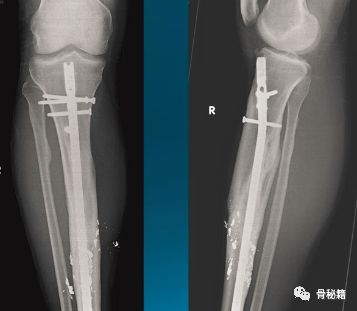

一个多阶段的胫骨骨折,看着移位不大

植入髓内钉后……

这样的骨折肯定长不上了,病人看了估计都会天天找你吧?翻修,近端加阻挡钉,小钢板